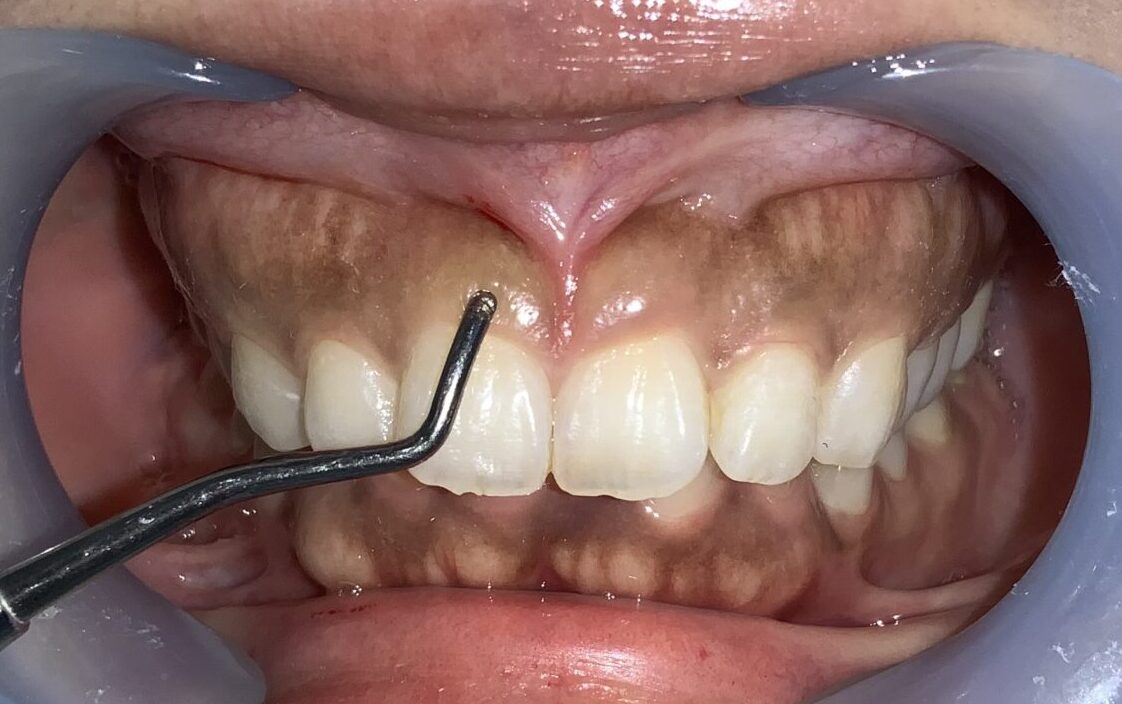

まずは手術前の状態です。

歯に歯ぐきがたくさんかぶっている状態です。

まずは歯ぐきのかぶり具合、歯ぐきの厚み、歯槽骨の状態、歯ぐきの切除範囲の検査からです。

このくらいかぶっていますから、綺麗に切除できます。